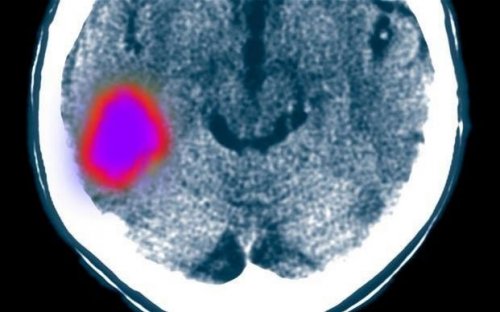

Ученые из Стэнфордского университета смогли поставить на ноги жертв тяжелых инсультов, проведя им инъекции стволовых клеток прямо в мозг. Без этого лечения пациентов ожидал бы паралич в течение всей их оставшейся жизни.

18 пациентов дали свое согласие на просверливания дыр в черепе и инъекции стволовых клеток в поврежденную часть их мозга, которые провели ученые из США. Эта экспериментальная методика лечения инсульта дала потрясающие результаты в деле восстановления подвижности пациентов. Более того, она подействовала в отношении тех, кто перенес инсульт и за несколько месяцев и даже лет до начала экспериментального лечения. Ранее наука была убеждена, что через 6 месяцев после инсульта мозг уже не способен регенерироваться.

Однако новая терапия эффективно вернула мозг взрослых людей в состоянии младенцев, чтобы он смог себя восстановить. Ученые из Стэнфордского университета полагают, что это терапия также сможет работать при лечении других нейродегенеративных недугов, вроде болезней Альцгеймера и Паркинсона, а также бокового амиотрофического склероза.

«Восстановление, которые мы наблюдали у многих из этих хронических пациентов с инсультом, было удивительным, - говорит профессор Гэри Стейнберг, глава отделения неврологии и нейрохирургии в Стэнфорде, который потратил 15 лет на изучение стволовых клеток. - И это было совсем не из той серии, что они «не могли двигать пальцами, а теперь могут». Прикованные к инвалидным коляскам пациенты встали на ноги и пошли. Их способность к передвижениям достаточно эффективно восстановилась. Это совершенно беспрецедентно. Результаты нашего исследования опровергают предыдущее мнение о том, что пациенты не способны восстанавливаться после первых 6 месяцев, следующих за инсультом, из-за гибели связей в мозге или невосполнимого ущерба. Совершенно очевидно, что связи в мозге могут восстанавливаться с помощью этого лечения, и мы все еще изучаем его невероятные перспективы».